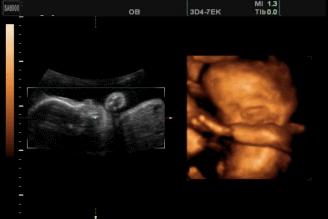

苗苗怀孕5个半月的时候去做四维彩超,她一直注视着大屏幕上宝宝的一举一动。忽然,她看到胎宝宝咧嘴笑了,这给她大大的惊喜,同时,她又很惊讶,宝宝在肚子里也会笑?常听说宝宝出生后还不会笑呢?

其实,关于胎宝宝在肚子里微笑,类似的报道并不少见,很多妈妈反馈过做四维时看到宝宝笑的样子,国外媒体也经常报道类似的新闻。

2003年,英国《卫报》报道,科学家用4D超声波成像系统拍到了26周宝宝微笑的图片。

2018年,英国《每日邮报》报道,一对夫妇在做四维彩超时发现宝宝咧嘴微笑,让父母感到喜出望外。

见诸各大网站的3D胎儿图像,也展示了胎儿在19周时微笑的模样,栩栩如生,惹人喜爱。

怀孕5个半月,胎儿已经有了面部表情,喜怒哀乐都会有,当然胎儿也会发笑。

5个半月的胎儿相当于22周,眼睛、鼻子、眉毛、耳朵、嘴巴等五官面貌结构完整,嘴巴、眉毛活动自如,面部表情丰富也很正常。

从这里看出,在做四维彩超的时候很容易捕捉到胎儿的微笑,这时不要觉得奇怪,这是胎儿正常的生理反应。